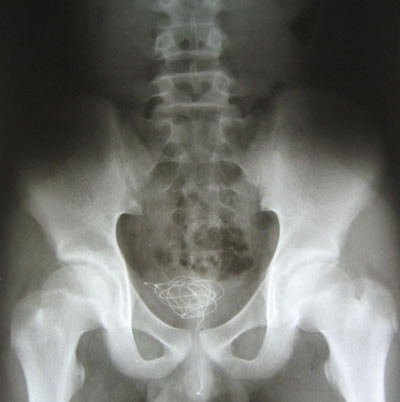

| Sợi dây điện nằm gọn trong bàng quang của trẻ. |

Xét nghiệm hình ảnh, các bác sĩ thấy cả sợi dây nằm gọn trong bàng quang của P., với một đầu còn nằm lửng lơ trong niệu đạo. Khi “vật chứng” được lấy ra ngoài, các bác sĩ đều ngạc nhiên vì sợi dây điện dài đến 1 m, đường kính khoảng 3 mm, lõi đồng còn bọc nhựa.

“Thế mà P. kể khi nhét hết cả sợi dây điện đường kính 3 mm vào lỗ tiểu lại không hề thấy đau đớn. Trong khi tất cả các bệnh nhân được đặt ống thông tiểu (sợi dây còn nhỏ và mềm hơn dây điện) đều kêu đau”, bác sĩ Thạch nói.

Theo bác sĩ, đây là trường hợp may mắn vì hai đầu lõi đồng của sợi dây điện không lộ ra nếu không đã có thể gây rách niệu đạo, bàng quang của P. Phần may mắn tiếp theo là sợi dây dài như thế mà không tạo nút thắt nên bác sĩ có thể nội soi gắp dị vật qua đường tự nhiên, chứ không cần mổ mở ổ bụng.

“Trường hợp này, nếu không được kịp thời xử lý, dị vật có thể tiếp tục di chuyển, bị lạc trong cơ thể, gây nhiễm trùng bàng quang, niệu đạo, đặc biệt là nhiễm trùng thận. Khi thận bị tổn thương thì sẽ gây hậu quả lớn, ảnh hưởng đến chức năng sinh lý sau này”, bác sĩ Thạch đánh giá.